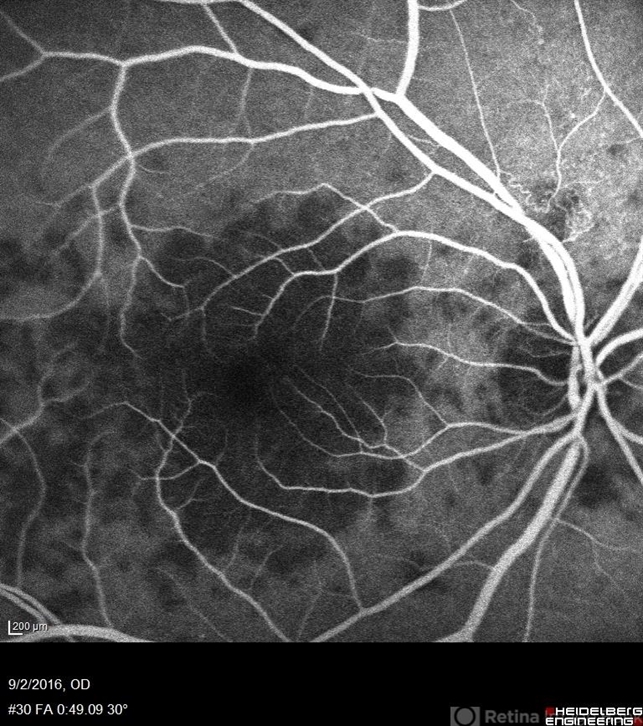

- Fluorescein angiography of a 68-year-old woman with decreased vision for past few months following viral illness.